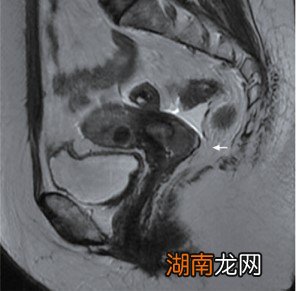

患者放疗前盆腔MRI图像示宫颈环周略长T2高信号 (箭头)